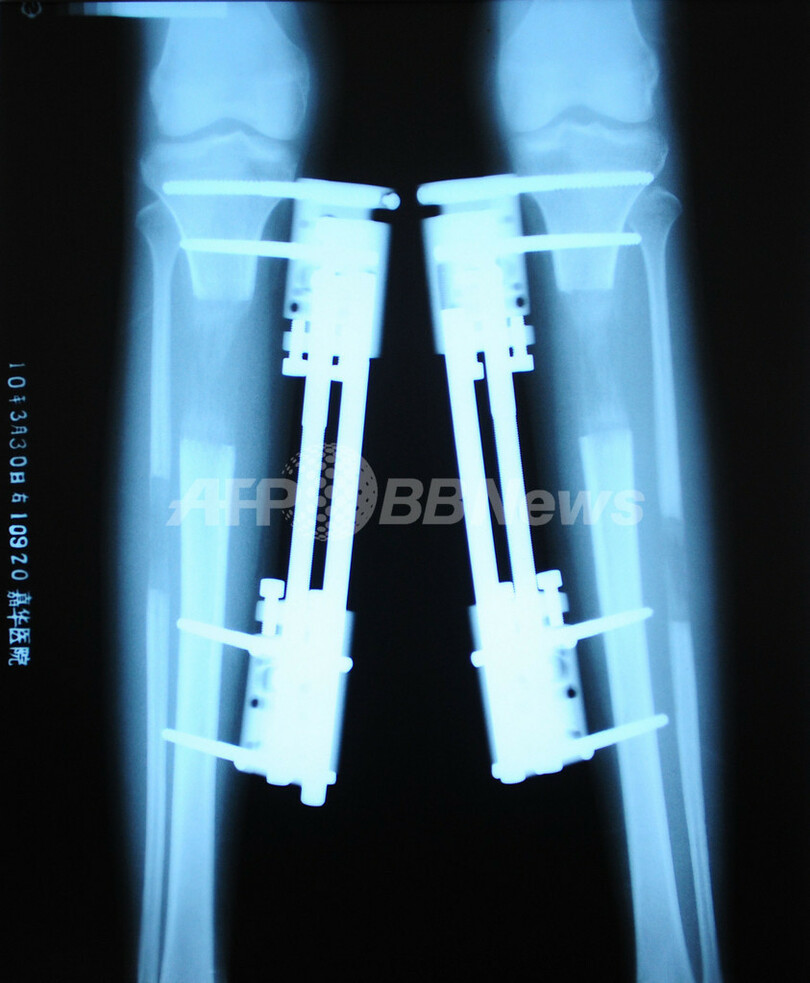

まず、骨髄には一切触れずに、膝下の脛(けい)骨と腓(ひ)骨のみを切断する。1週間後、両方の骨が再生しはじめたところで、重量約500グラムのニッケル・チタン製固定器を足の内部にねじ込む。

その後4か月間、毎日、固定器を拡張して、少しずつ足を伸ばしていく。6~8センチ伸ばすのに4か月はかかるという。骨が強くなって歩けるようになるまでには、さらに4か月を要する。